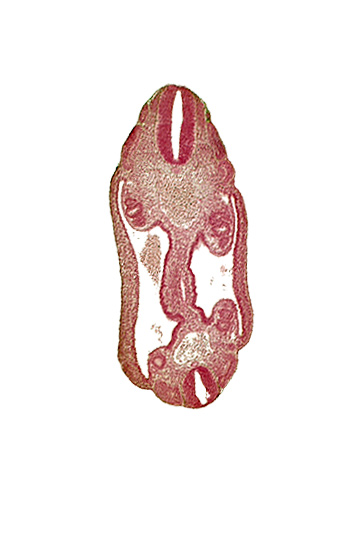

Carnegie Embryo #836 | Location: 12-03-06

Keywords: aorta, coelom, dermatomyotome 16 (T-4), dermatomyotome 17 (T-5), dermatomyotome 25 (L-1), mesonephric duct, mesothelium, neural tube, notochord, sclerotome, somatic mesoderm, splanchnic mesoderm

Source: The Virtual Human Embryo.